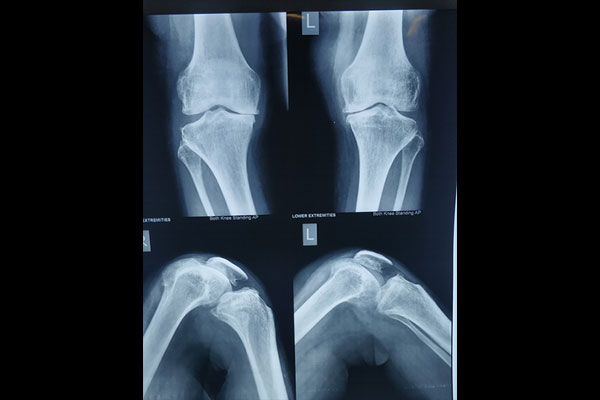

STEPS OF HTO